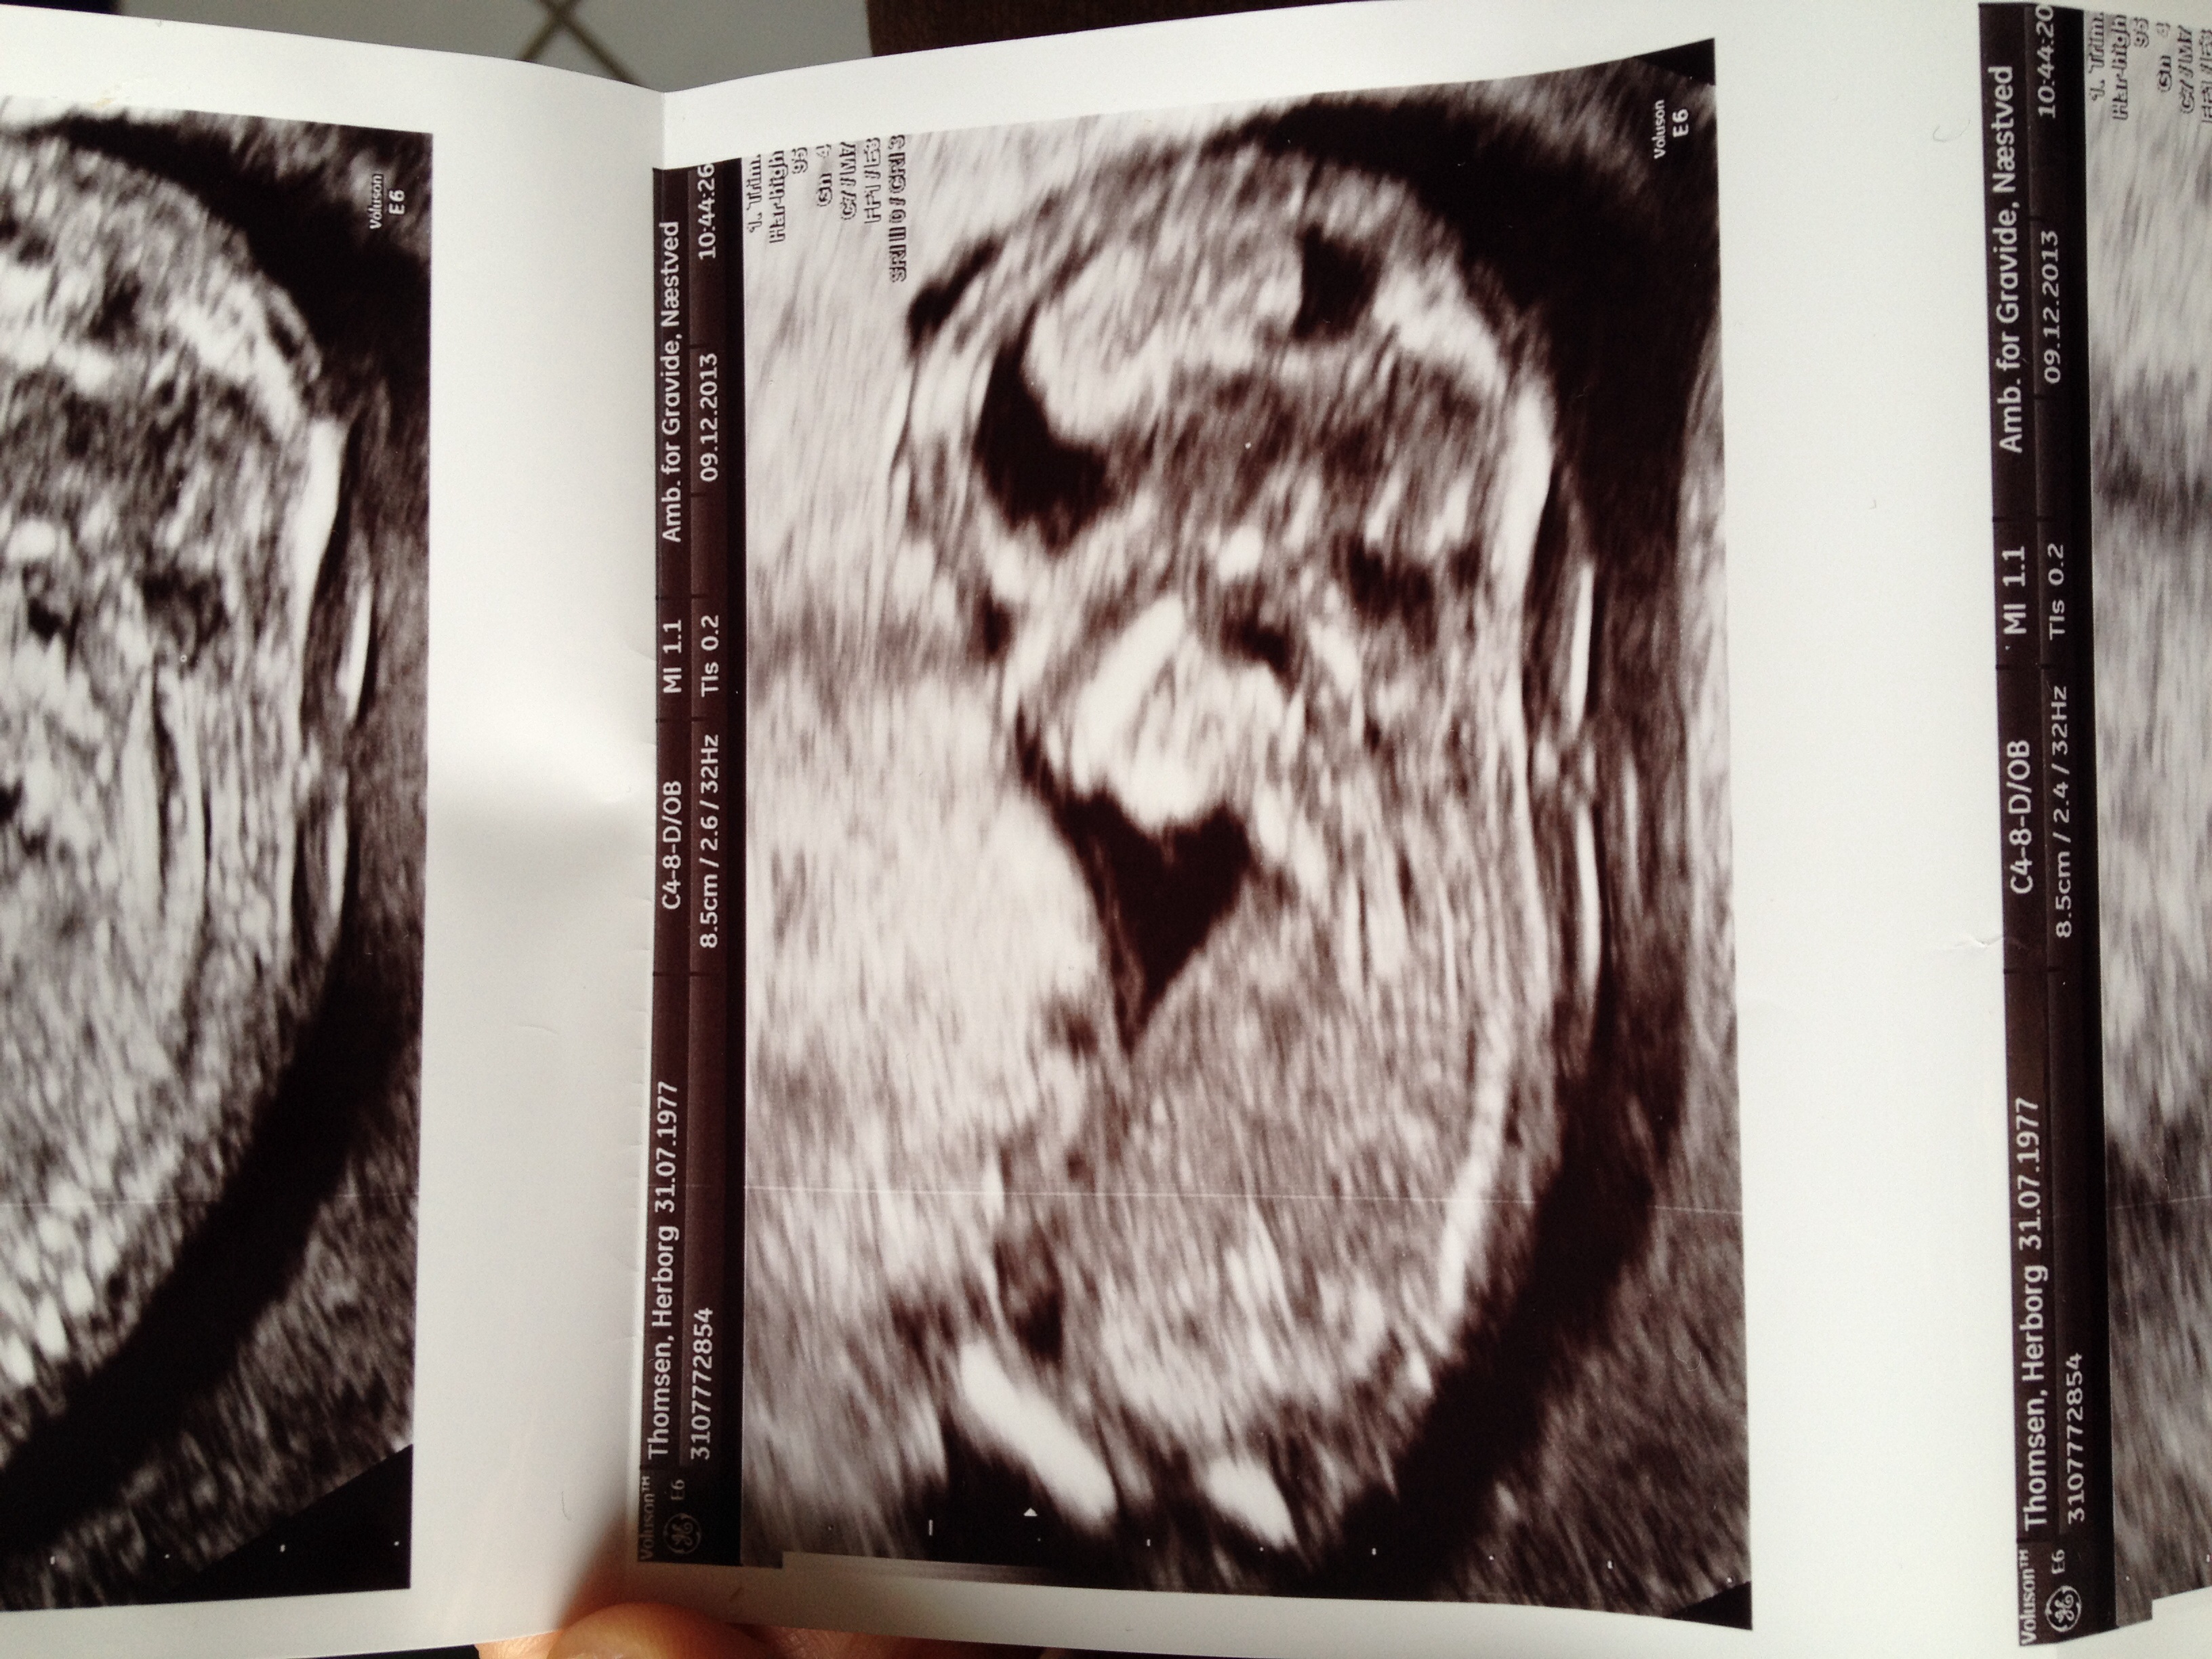

Leaning girl. How far along are you?

First pic I'd say girl x

Girl

I think I remember something about upside down babies not being accurate for nub guessing. Although I can't quite grasp why not. The shape in the first shot looks boyish to me. But angle is girl (which you normally go off of...but I don't know how accurate it is with the upside down thing, ya know!). Sorry, I'm no help.